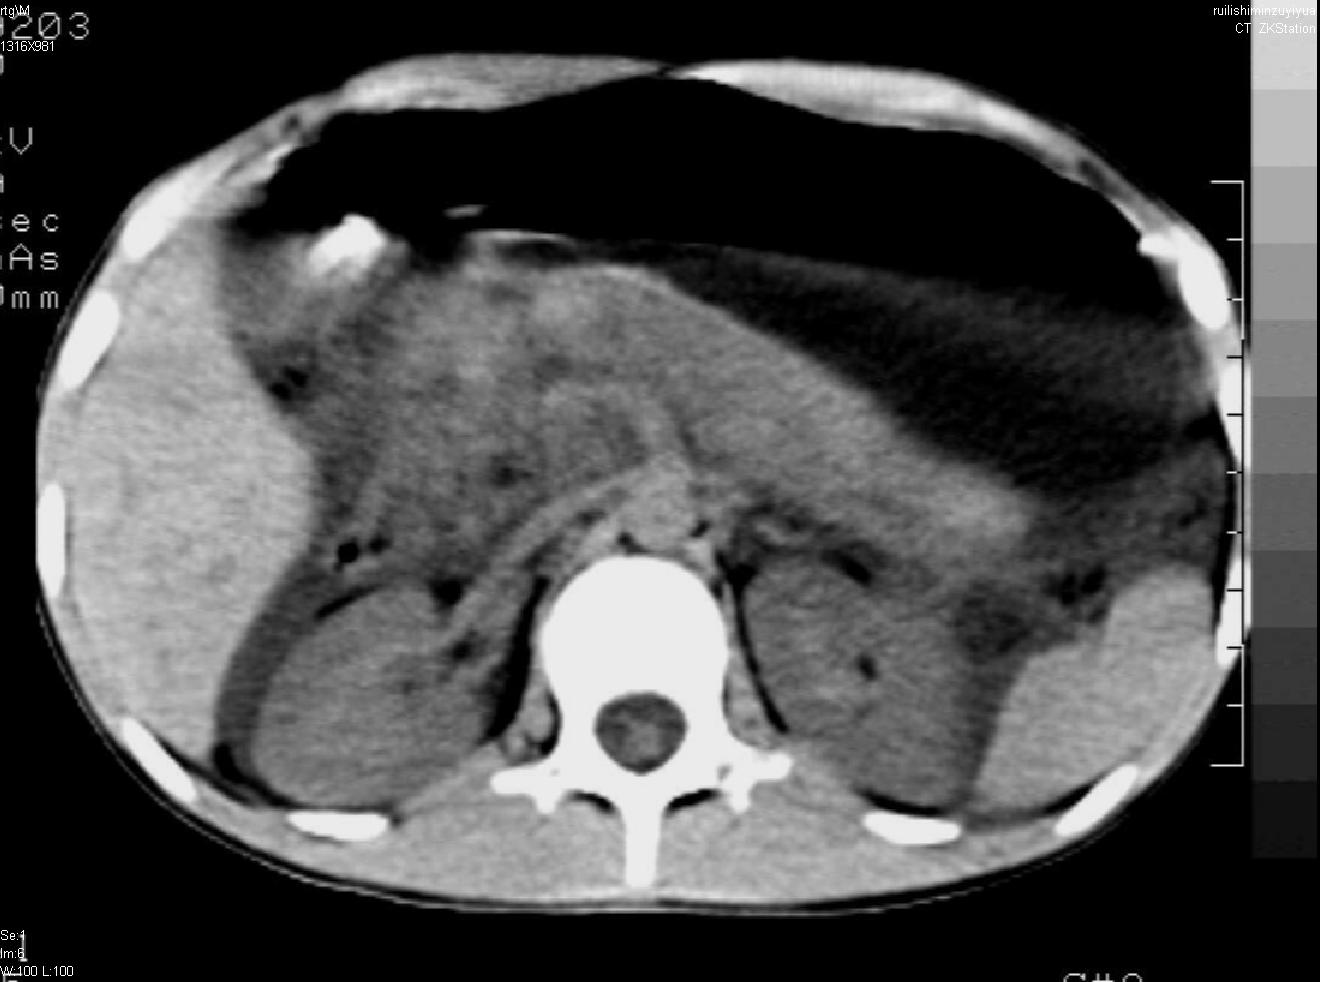

标题: PED0282:女,10岁,上腹疼痛2周 [打印本页]

标题: PED0282:女,10岁,上腹疼痛2周

b超:胆囊结石。疑坏死性胰腺炎

支持小儿急性坏死性胰腺炎。

支持急性胰腺炎并腹膜炎。